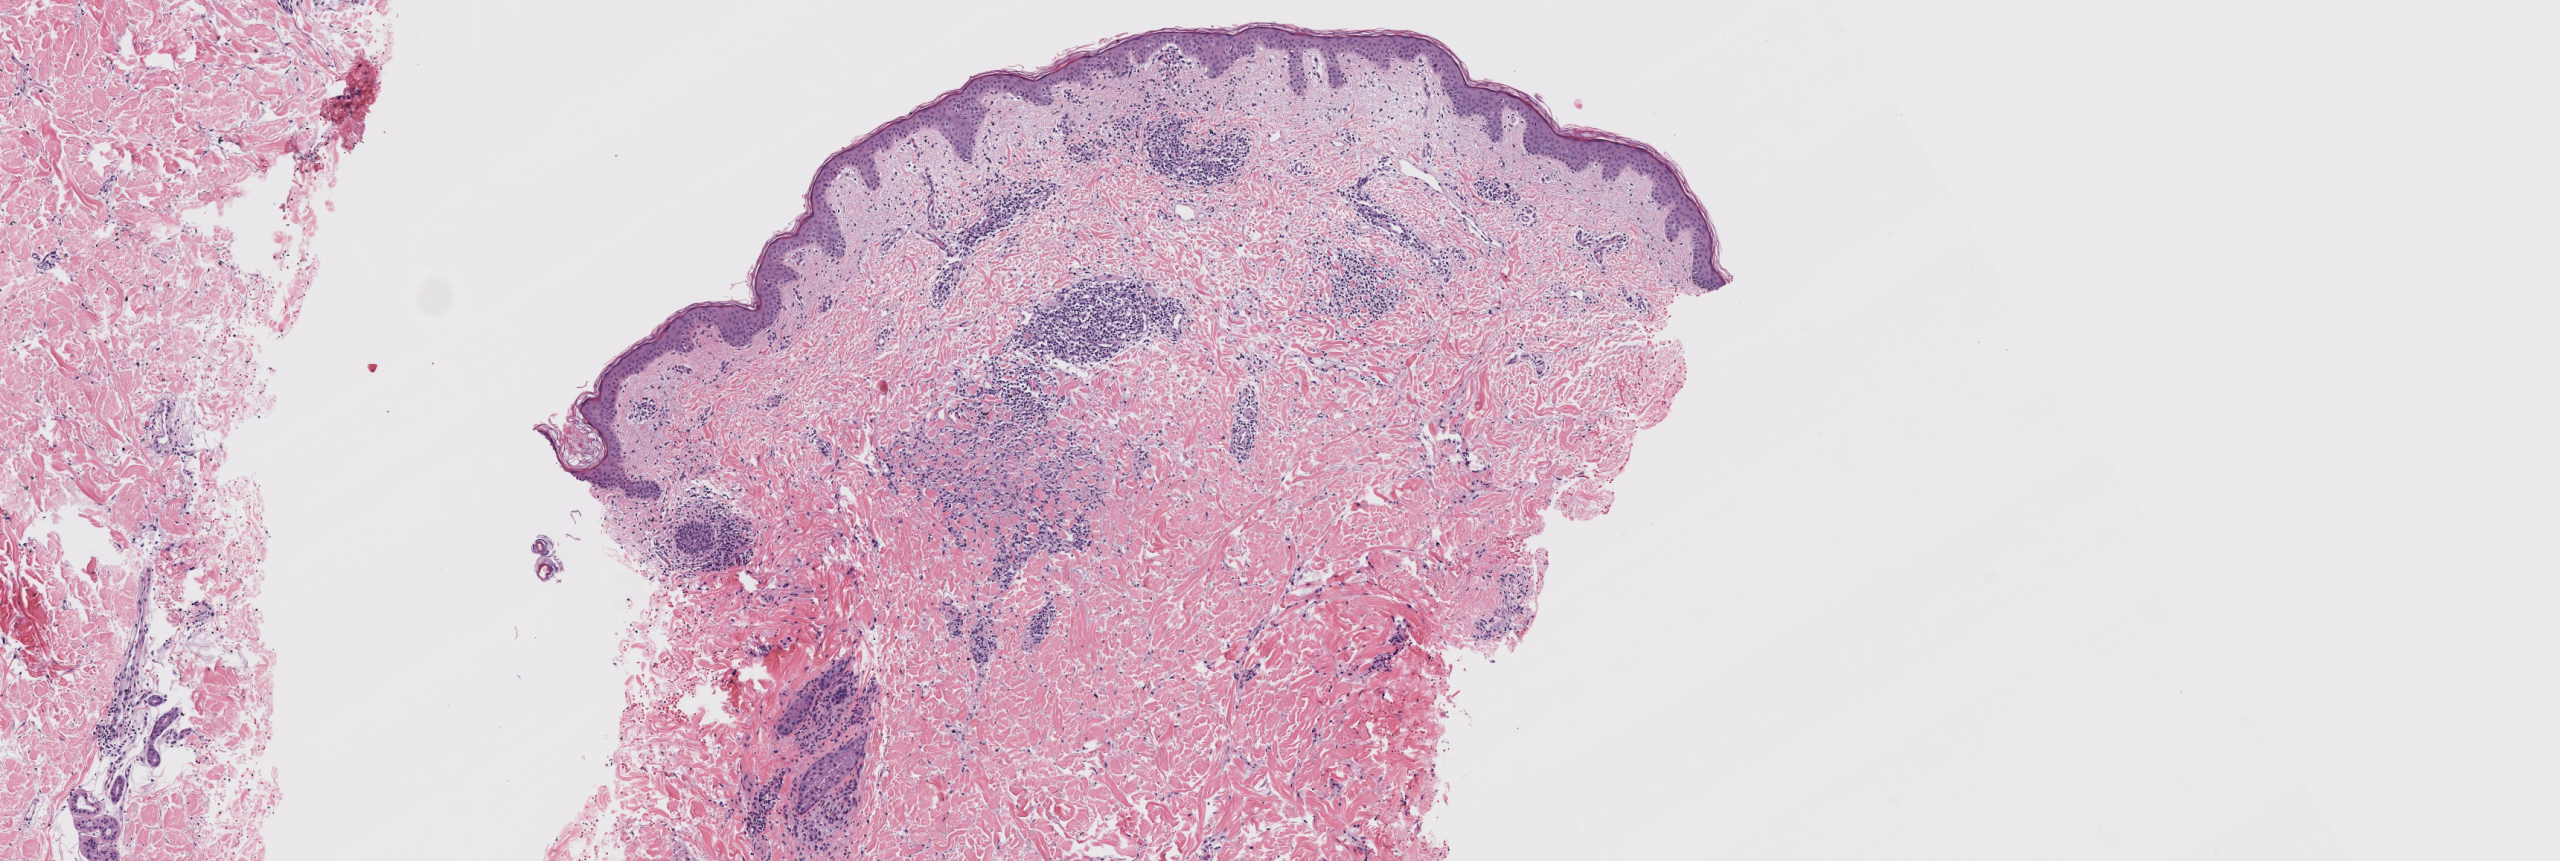

[Image 1: Low-power histologic view showing subtle interstitial infiltrate]

This is patch-type granuloma annulare, an uncommon but increasingly recognized variant of classic GA. The diagnosis is confirmed by the interstitial pattern of bland mononuclear histiocytes dissecting between preserved collagen bundles with increased dermal mucin and absence of epidermal changes or palisaded granulomas.